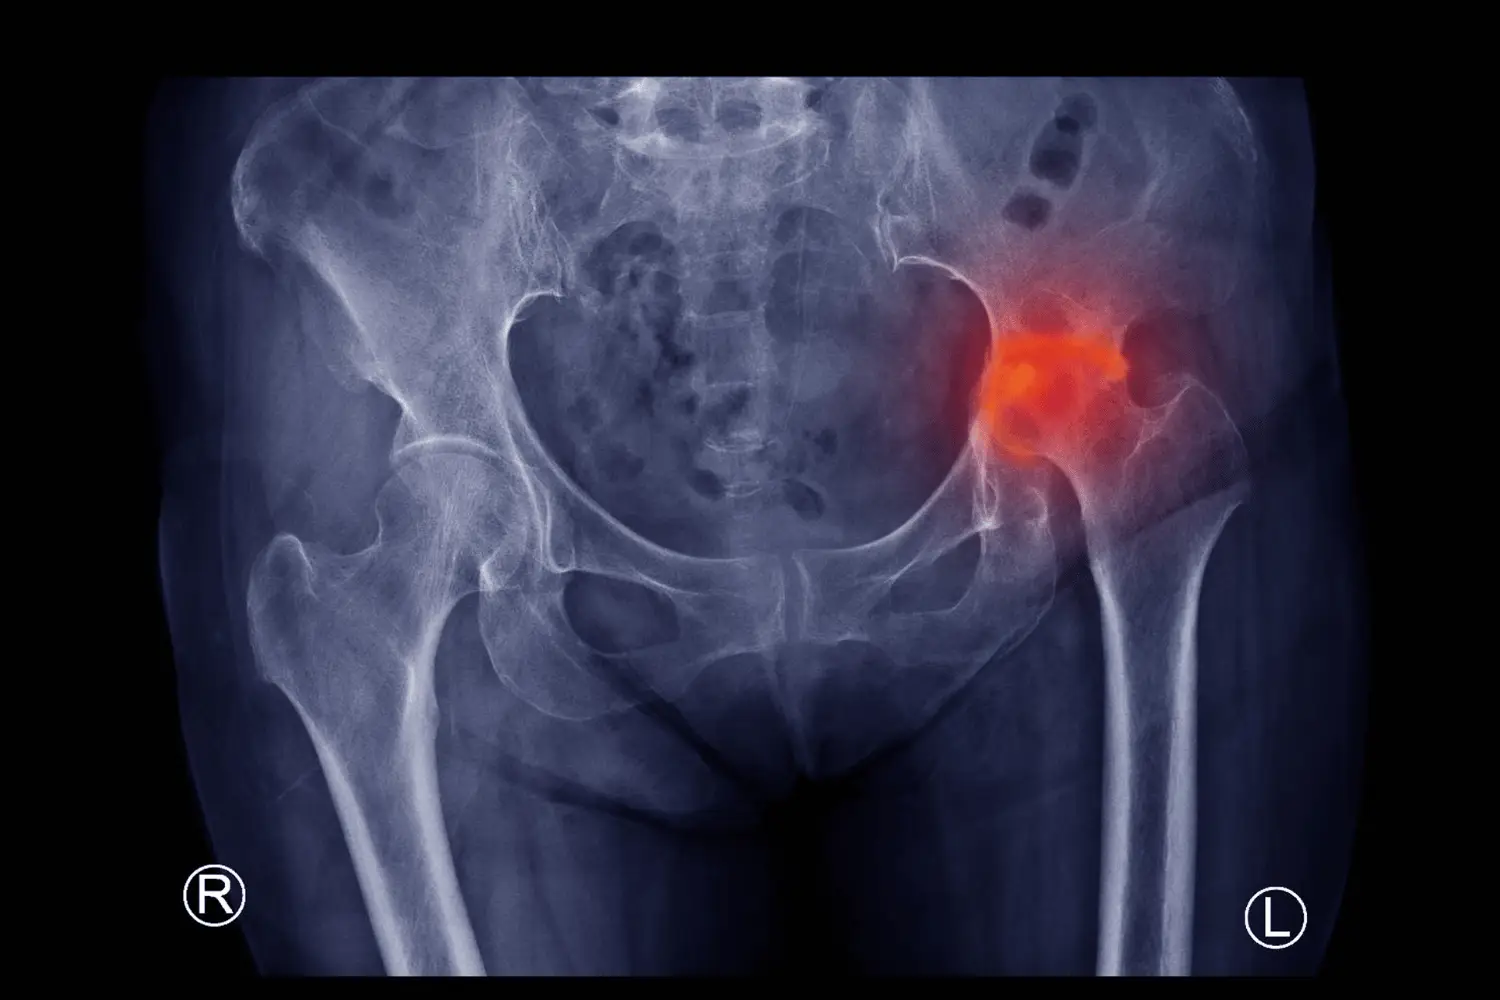

Hip Fractures